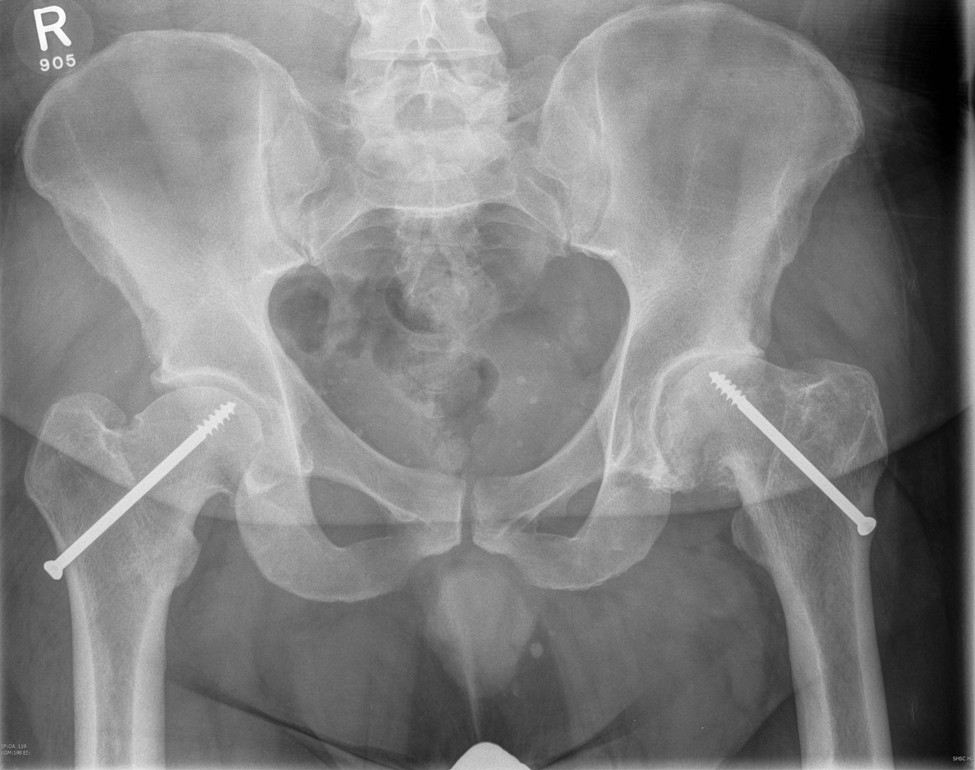

Secondary OA

SUFE Perthes

DDH Protrusio

Trauma

Paget's AVN